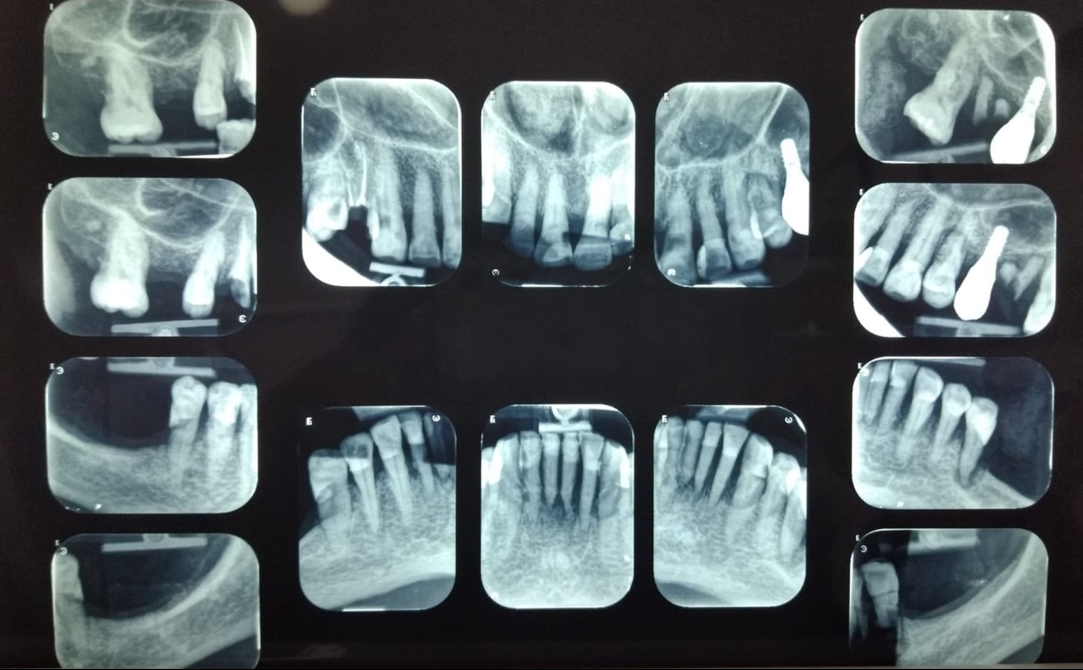

Radiografía seriada